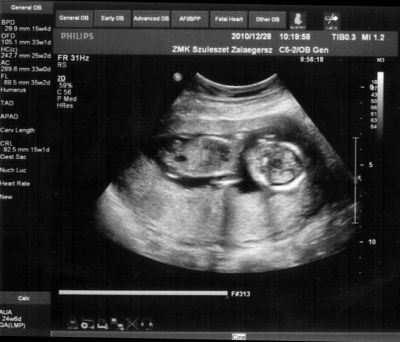

Bár tegnap a dokor bácsi azt mondta, hogy azért lassan vissza kellene vennem a lendületből, mert nem lesz jó vége. Manócska jól van, de tegnap nem tudtuk megnézni. Hasi uh-val próbálkozott, de pont úgy fordult, hogy csak a nagy kobakját láttuk

Gondolta, ha arra van a feje, akkor lentről lehet látni valamit a neméből.

Be is terpesztett rendesen, mint egy kis utcalány

Természetesen lánynak is látszott, bár azt mondta, hogy még ne éljük bele magunkat. A férjem le is tört egy kicsit, de nem vallotta volna be.Holnap reggel megyek AFP-re.